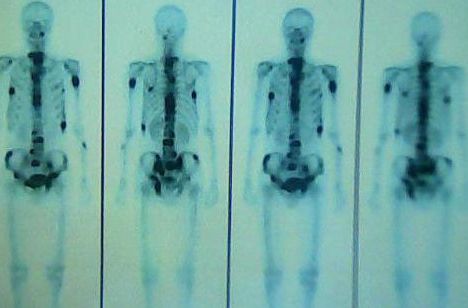

建立经骨髓注射肺转移和术后复发模型,揭示骨髓注射法构建模型的优越性和可行性,为研究恶性肿瘤肺转移提供新的研究基础...